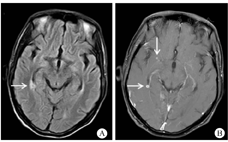

患者男,36岁,因"发现HIV抗体阳性5个月,发热、咳嗽、淋巴结肿痛3个月"于2019年3月15日入院。患者2018年11月10日确诊抗-HIV(+),查CD4+T淋巴细胞计数25个/μL,血浆HIV载量未检测,当时颈部有数枚淋巴结肿大,约1 cm×1 cm大小,无疼痛及不适,未作检查明确病因及给予特殊治疗。11月15日当地医院予拉米夫定(0.3 g/d)、替诺福韦(0.3 g/d)和依非韦伦(0.6 g/d)联合ART,12月15日患者开始出现发热,热峰40 ℃,咳嗽,少量白黏痰,颈部淋巴结进行性增大,并出现全身多处淋巴结肿痛。2019年1月10日当地医院淋巴结穿刺脓液以及肺泡灌洗液GeneXpert MTB/RIF检测阳性(无利福平耐药),诊断为"艾滋病合并肺结核、淋巴结核"。1月14日启动"异烟肼、乙胺丁醇、莫西沙星以及利福平"抗结核治疗2月余。1月15日测血浆HIV载量为200拷贝/mL。治疗后患者淋巴结肿痛仍进行性加重,咳嗽无明显好转,反复发热,遂来我院就诊。既往体健。入院体格检查:体温36.5 ℃,呼吸20次/min,脉搏120次/min,血压89/68 mmHg(1 mmHg=0.133 kPa),耳下、颌下、颈部、锁骨上、腋窝淋巴结肿大,伴触痛,部分有波动感。口腔无白斑,双肺呼吸音粗,未闻及干湿性啰音,心律齐,各瓣膜区未闻及杂音,腹软,无压痛及反跳痛,肝脾肋缘下未及肿大,肠鸣音正常,双下肢无水肿。入院后立即完善相关检查,血常规示白细胞(WBC)8.33×109/L,中性粒细胞占比0.852,血红蛋白(Hb)137 g/L,血小板360×109/L。C-反应蛋白(CRP)73.2 mg/L,降钙素原(PCT)0.12 ng/L,红细胞沉降率60 mm/1 h。CD4+T淋巴细胞计数162个/μL,血浆HIV载量低于检测值下限。血清1,3-β-D-葡聚糖104.0 pg/mL,半乳甘露聚糖0.25,隐球菌抗原阴性。痰抗酸染色阳性,GeneXpert MTB/RIF检测阳性(无利福平耐药),痰细菌培养阴性。淋巴结穿刺脓液抗酸染色阳性,GeneXpert MTB/RIF检测阳性(无利福平耐药),脓液细菌培养阴性。结核分枝杆菌耐药基因检测示异烟肼、利福平、乙胺丁醇、莫西沙星以及阿米卡星均敏感。3月15日查胸部CT:肺部弥漫性病变,示蜂窝状高密度影,支气管壁增厚,呈囊状或柱状扩张,间有多发小片状、粟粒状高密度影,边界欠清,密度欠均(图1)。患者无中枢神经系统症状,3月22日常规筛查颅脑磁共振示:颅内多发病灶,右侧脑室旁及基底节区小片状T2高信号,增强后可见结节样强化及环形强化(图2)。3月23日完善脑脊液检查:WBC 2×106个/L,总蛋白344.2 mg/L,乳酸脱氢酶(LH) 14 IU/L,葡萄糖2.8 mmol/L,氯122 mmol/L,腺苷脱氨酶0.3 U/L;抗酸染色阴性,GeneXpert MTB/RIF阴性,隐球菌抗原阴性,脑脊液细菌培养阴性;干扰素γ 12 ng/L。

注:A.右侧脑室旁及基底节区小片状T2高信号(箭头示);B.增强后可见结节样强化及环形强化(箭头示),周围水肿带未见强化